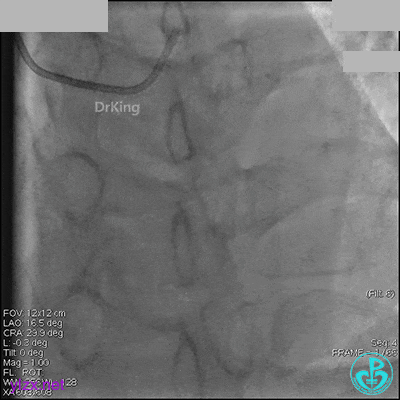

1周后再次上台,右冠脉3级血流,3段局限性严重狭窄,内膜模糊,应该是上次操作夹层遗留下的血肿。

先处理前降支开口严重狭窄并顺利植入前降支到左主干支架。